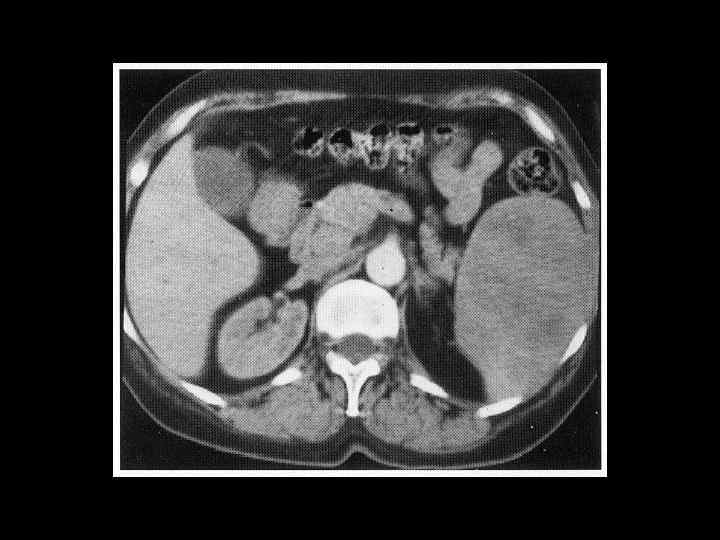

АКТУАЛЬНЫЕ ВОПРОСЫ РЕНТГЕНОЛОГИИ ЛУЧЕВАЯ ДИАГНОСТИКА ЗАБОЛЕВАНИЙ СЕЛЕЗЕНКИ Спленомегалия: Причины - Заболевания системы крови (гемолитические анемии, острые лейкозы, хронический миелоидный лейкоз, злокачественные лимфомы) - портальный цирроз печени - тромбоз селезеночной вены